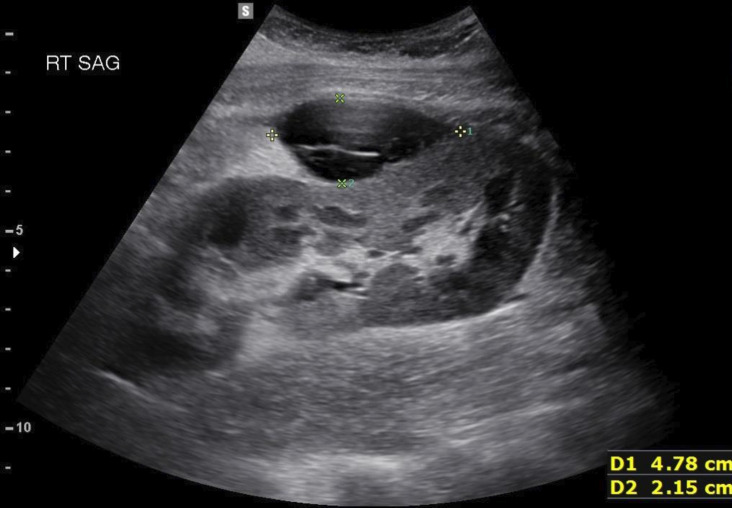

Lump in my side: transplanted kidney or something more?

我身边的肿块:移植的肾脏还是其他什么?